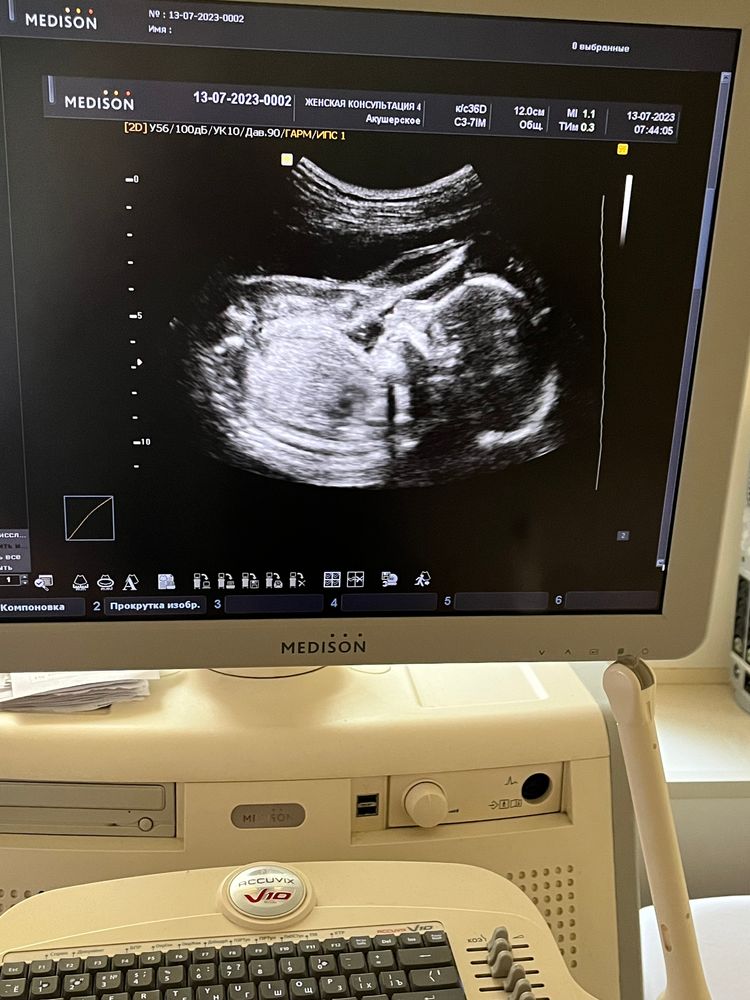

22 недели и 3 дня 🌸

Привет всем ! 30 июня был скрининг и отмены утрожестана , на всякий случай решила сходить на узи посмотреть как шейка и малыш

30.06 вес 402 грамма 27 см

13.07 вес 530 грамм 29 см 😆

а так фото с узи и вот такие мы акробаты 😂